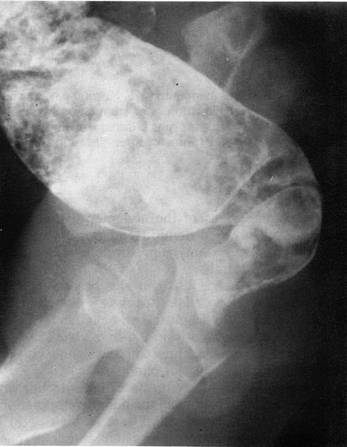

Examenul radiologic este important pentru diagnostic; sunt evidentiate: hiperkinezia gastrica, cu unde peristaltice care 'musca' profund curburile stomacului, fara sa poata determina trecerea bariului prin canalul piloric; in cazurile mai vechi stomacul apare dilatat, in special in regiunea antrala - dilatatie prepilorica - uneori cu aspect in chiuveta; evacuarea gastrica este foarte intarziata: in loc sa iasa din stomac in trei ore, bariul ramane aici 6-12 ore, uneori si 24 de ore; canalul piloric apare alungit (1-3 cm), subtire ca un fir, cu cele doua margini paralele si concave in sus si la stanga (imaginea difera de aceea a pilorului normal care este foarte scurt, uneori invizibil) realizand la extremitatile sale imagini biconcave, cu godeuri laterale, semn al 'umbrei' pe care o face tumora pilorica pe antru si pe bulbul duodenal . Imaginea directa de hipertrofie pilorica (canal piloric alungit cu cele doua imagini paralele si concave in sus si la stanga) este cea care determina conduita chirurgicala; semnele de staza gastrica si chiar absenta pasajului piloric a produsului opac nu sunt suficiente.

Fig.: Stenoza hipertrofica de pilor. Se evidentiaza alungirea canalului piloric.